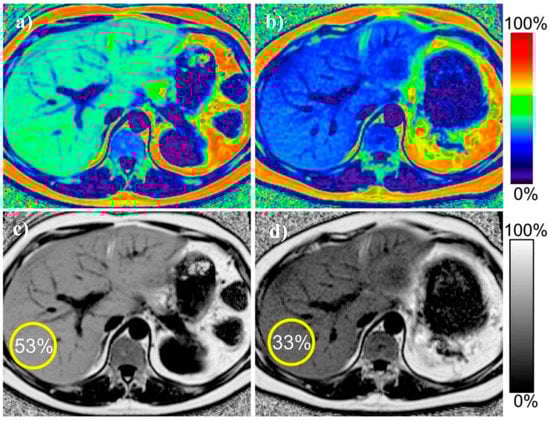

3. Magnetic Resonance Imaging Techniques